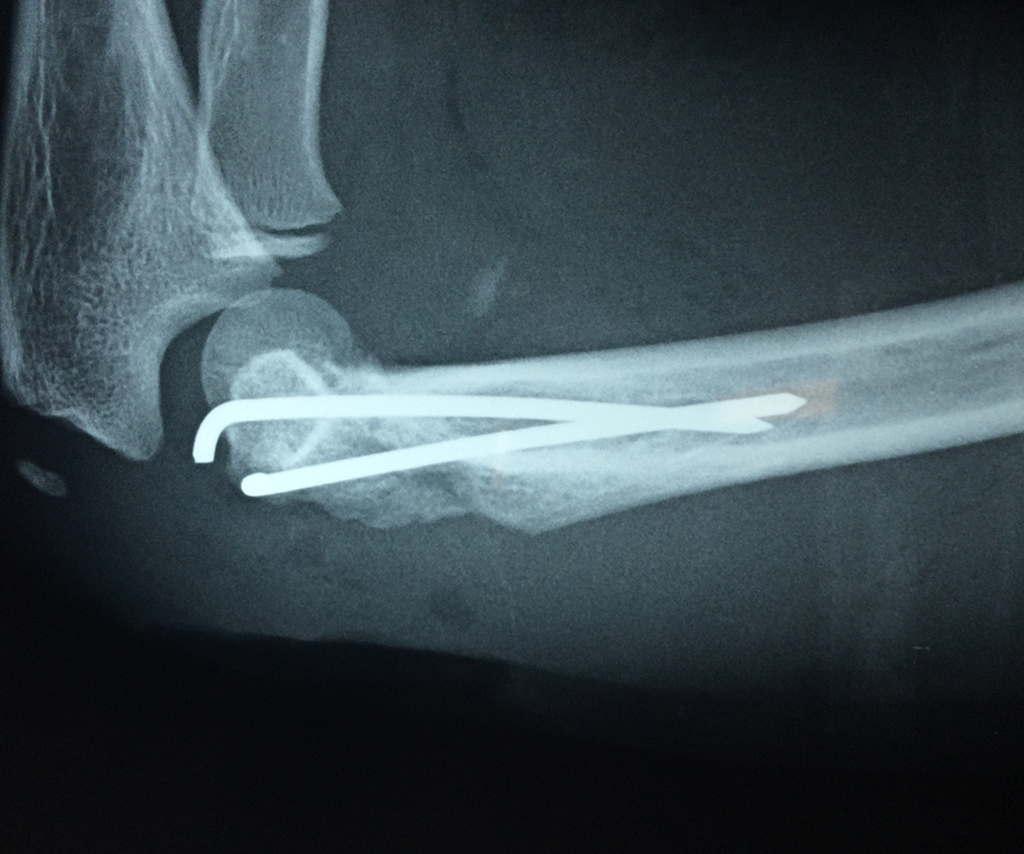

Los extremos óseos se conectan entre si por un conjunto de ligamentos que contribuyen a su fijación y están rodeado por una estructura común que se llama cápsula articular, en cuyo interior se encuentra el líquido sinovial.